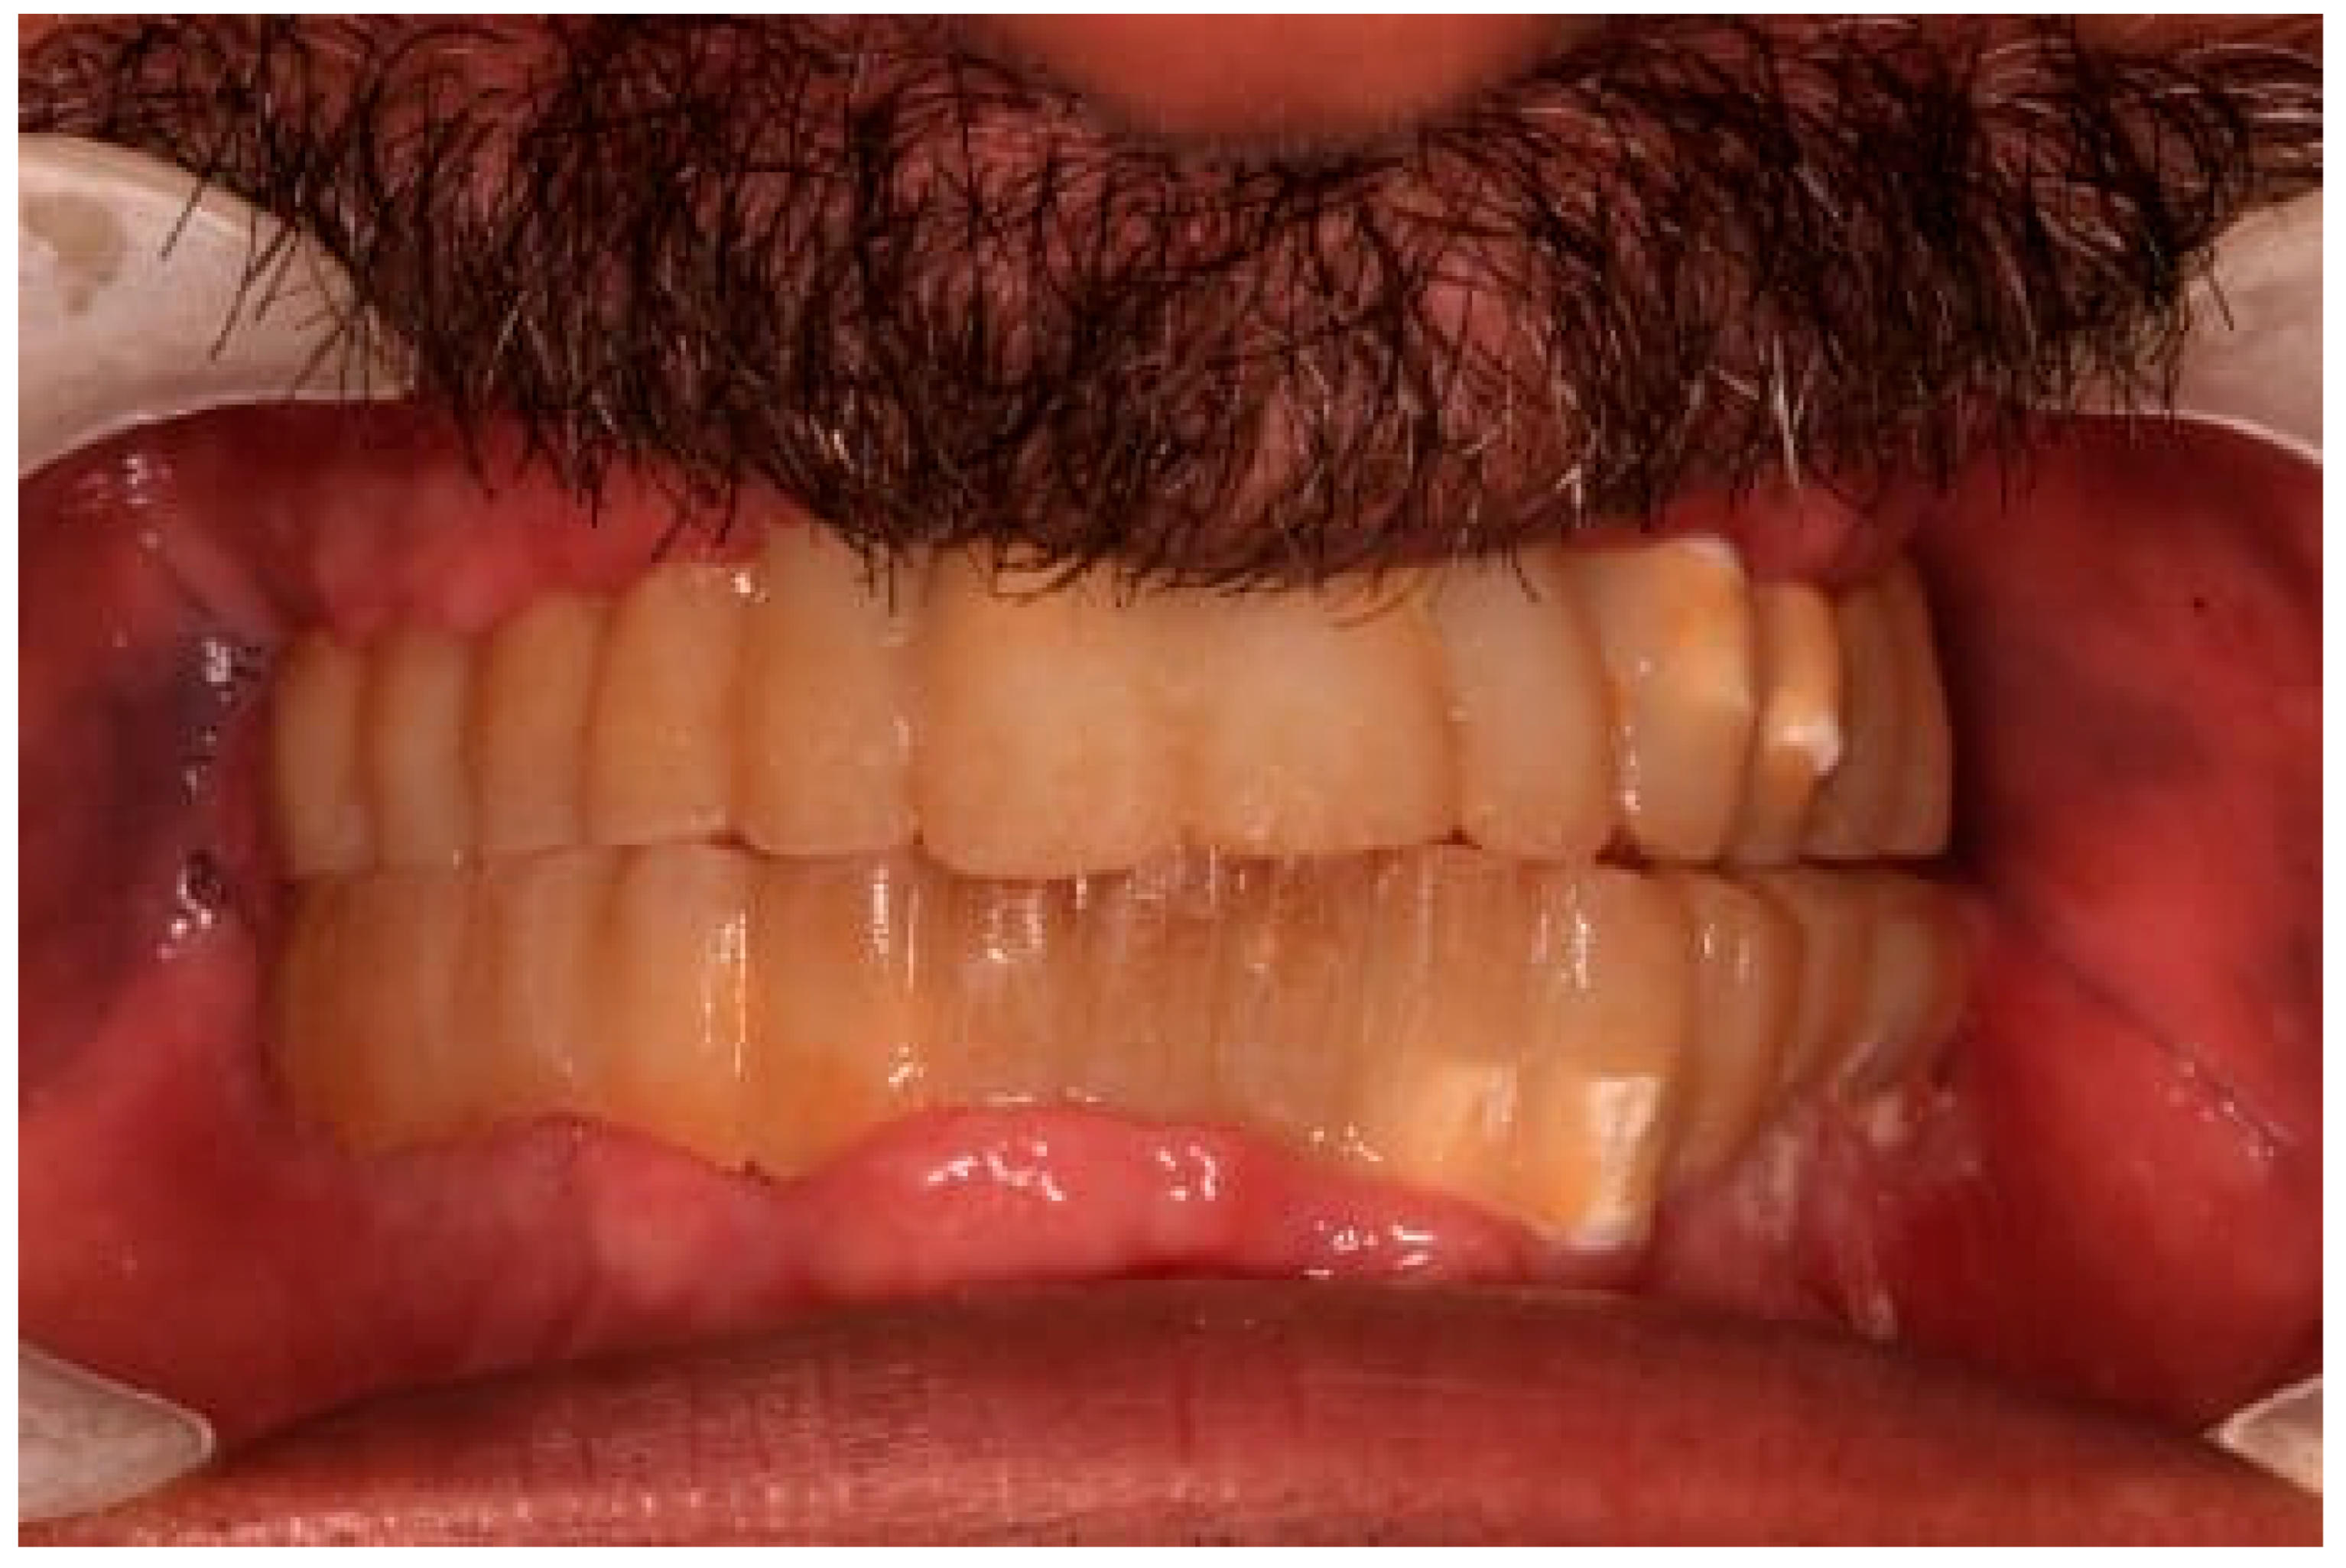

The restoration plan involved placing a bridge that connects the central incisors to the canines, along with an additional bridge spanning the first premolar to the first molar on each side of the maxillary arch. In the mandibular arch, the plan included three bridges: one connecting the lateral incisors bilaterally and another bridging the canines to the second premolars and first molars on each side (Figure 14 and Figure 15). Placing was confirmed using Panoramic radiographs obtained using the PantOs DG XP panoramic dental X-ray system (Fona S.r.l., Assago, Italy; CE 0051). The unit operates on a 230 V, 50/60 Hz input line with an 8 A fuse. Standard panoramic exposure parameters were applied (90 kVp, 10 mA, exposure time 14 s) following the manufacturer’s safety recommendations. A trained radiology technician performed all scans, and patient positioning was standardized using the built-in cephalostat support and light-beam alignment to ensure reproducibility of serial images.

2.6. Sixth Visit

During the three-year follow-up period from October 2022 through September 2025, the patient was regularly recalled for evaluation. The peri-implant soft tissues remained healthy throughout the observation period. The gingiva surrounding the implants was consistently pink, firm, and showed no bleeding or suppuration upon probing of the peri-implant sulcus. At the last visit, probing depths ranged from 2–4 mm (mean 3 mm) in the maxillary arch and 1–3 mm (mean 2 mm) in the mandibular arch. No clinical signs of inflammation, edema, or granulation tissue were observed, indicating stable peri-implant mucosa and sustained biocompatibility of the materials used. Radiographic assessment revealed no crestal bone loss, and the prosthetic components remained functionally and esthetically intact, with no evidence of wear, fracture, or loosening. The patient reported high satisfaction regarding comfort, function, and appearance, further supporting the clinical success and reliability of this treatment approach (Figure 16 and Figure 17).

Figure 15. Panoramic X-ray showing the final prostheses (taken 21 November 2023).

Figure 16. Follow-up photo.